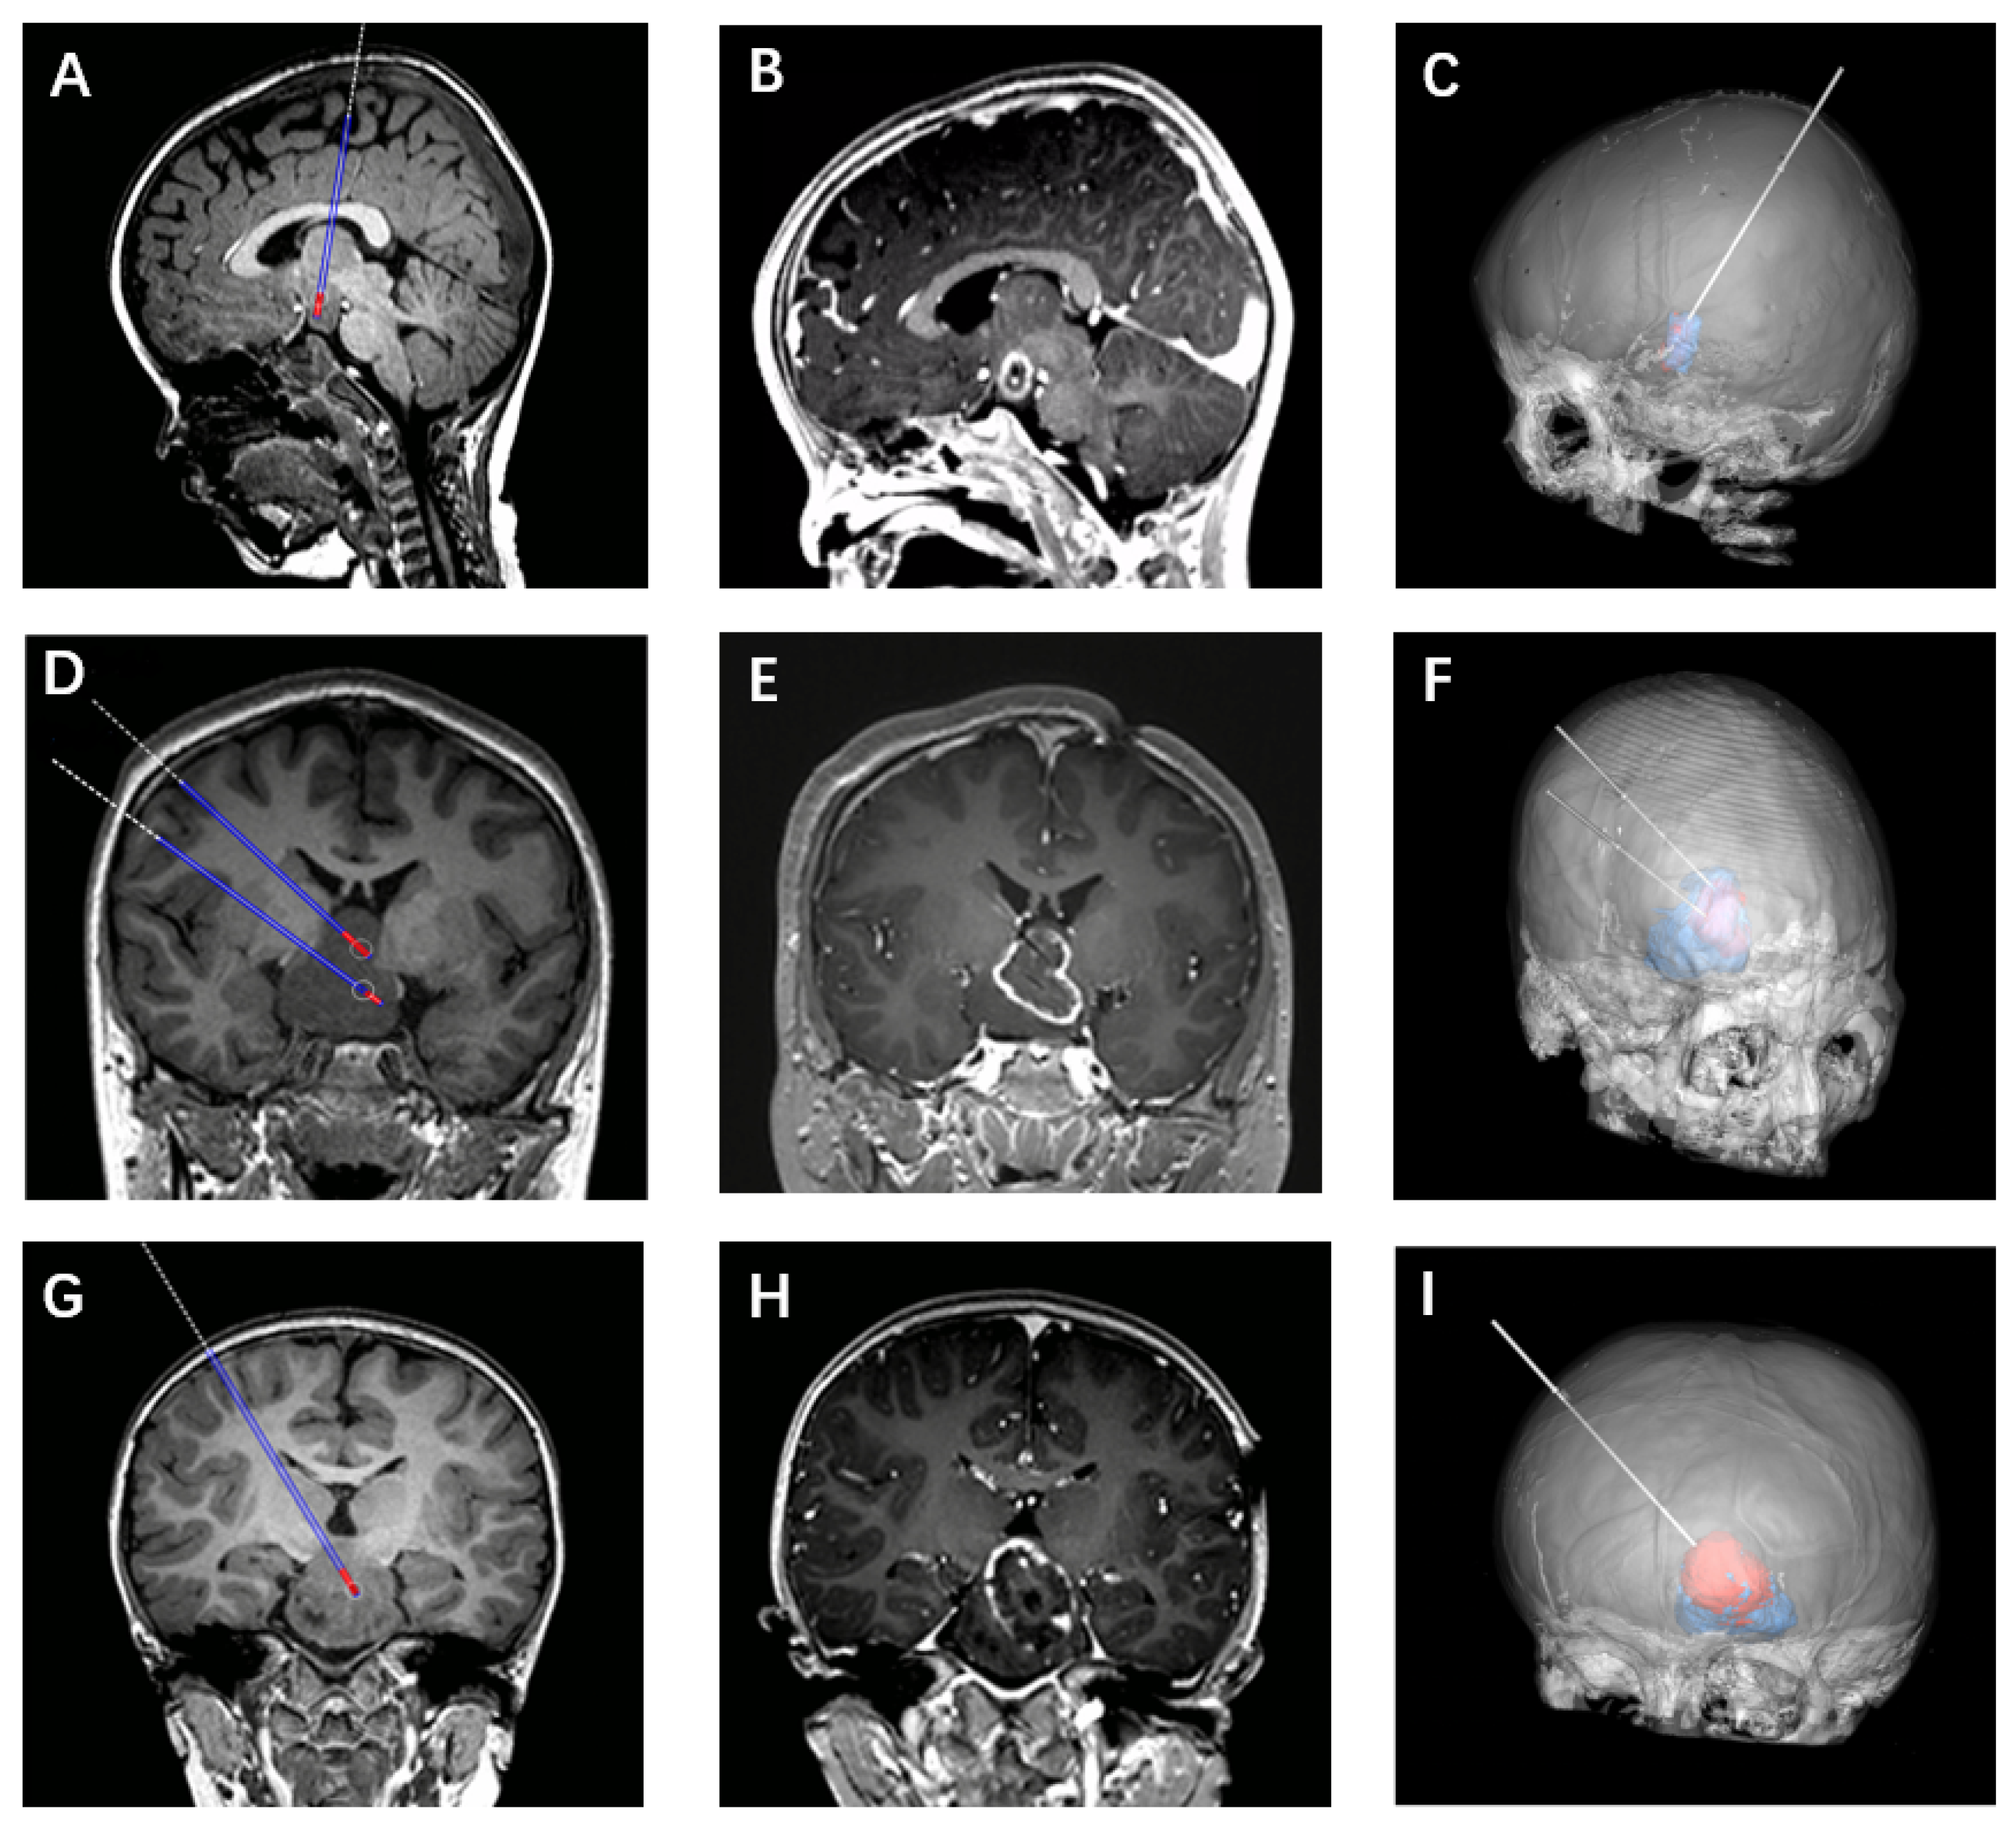

2.2. Surgical Procedure